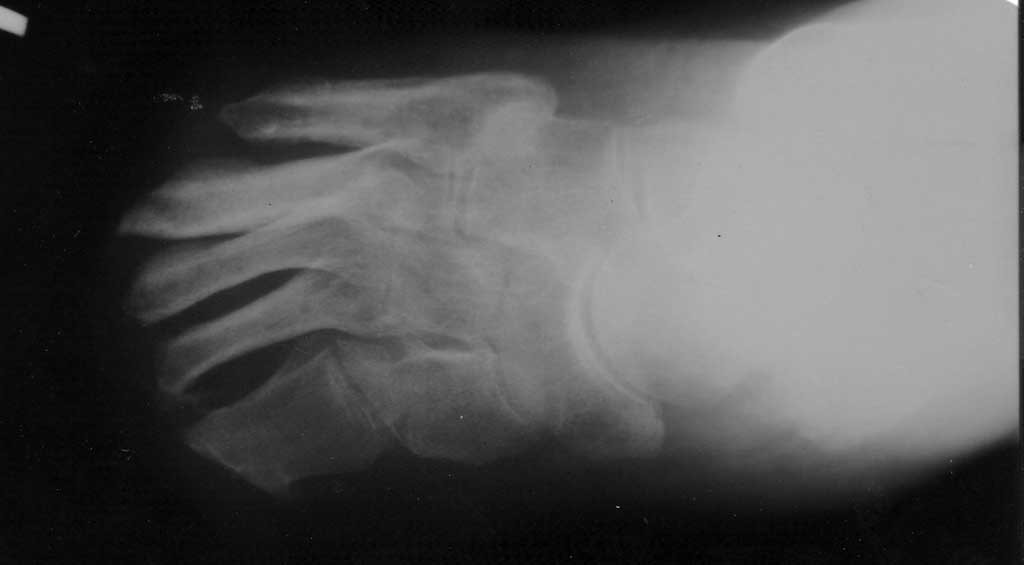

Уважаемые коллеги! Представляю пациента 56л.В 2008, 2009 и 2010гг трижды отморожения обеих

стоп с некрозом. Последовательно выполнены некрэктомия на уровне дистальных фаланг

пальцев, проксимальных фаланг и последняя на уровне плюсневых костей (2010). Впоследствие

на культе левой стопы сформировалась трофическая язва, настоящая госпитализация 6 марта

этого года. Пациент из тех, кого называют uncooperative patient. Живет один,

злоупотребляет алкоголем. Показатели сахара крови, общего белка и фракций, биохимические

показатели в пределах нормы. Сопутствующая патология - гиперт б-нь 2ст. Пульсация на задней

б/берцовой, подколенной и бедренной артериях отчетливая. УЗДГ, к сожалению, недоступно.

Прошу совета в плане тактики лечения. Сначала, естественно, некрэктомия, а потом?

Восстановление покровных тканей, оптимальный способ? Ампутация на уровне сустава

Лисфранка?